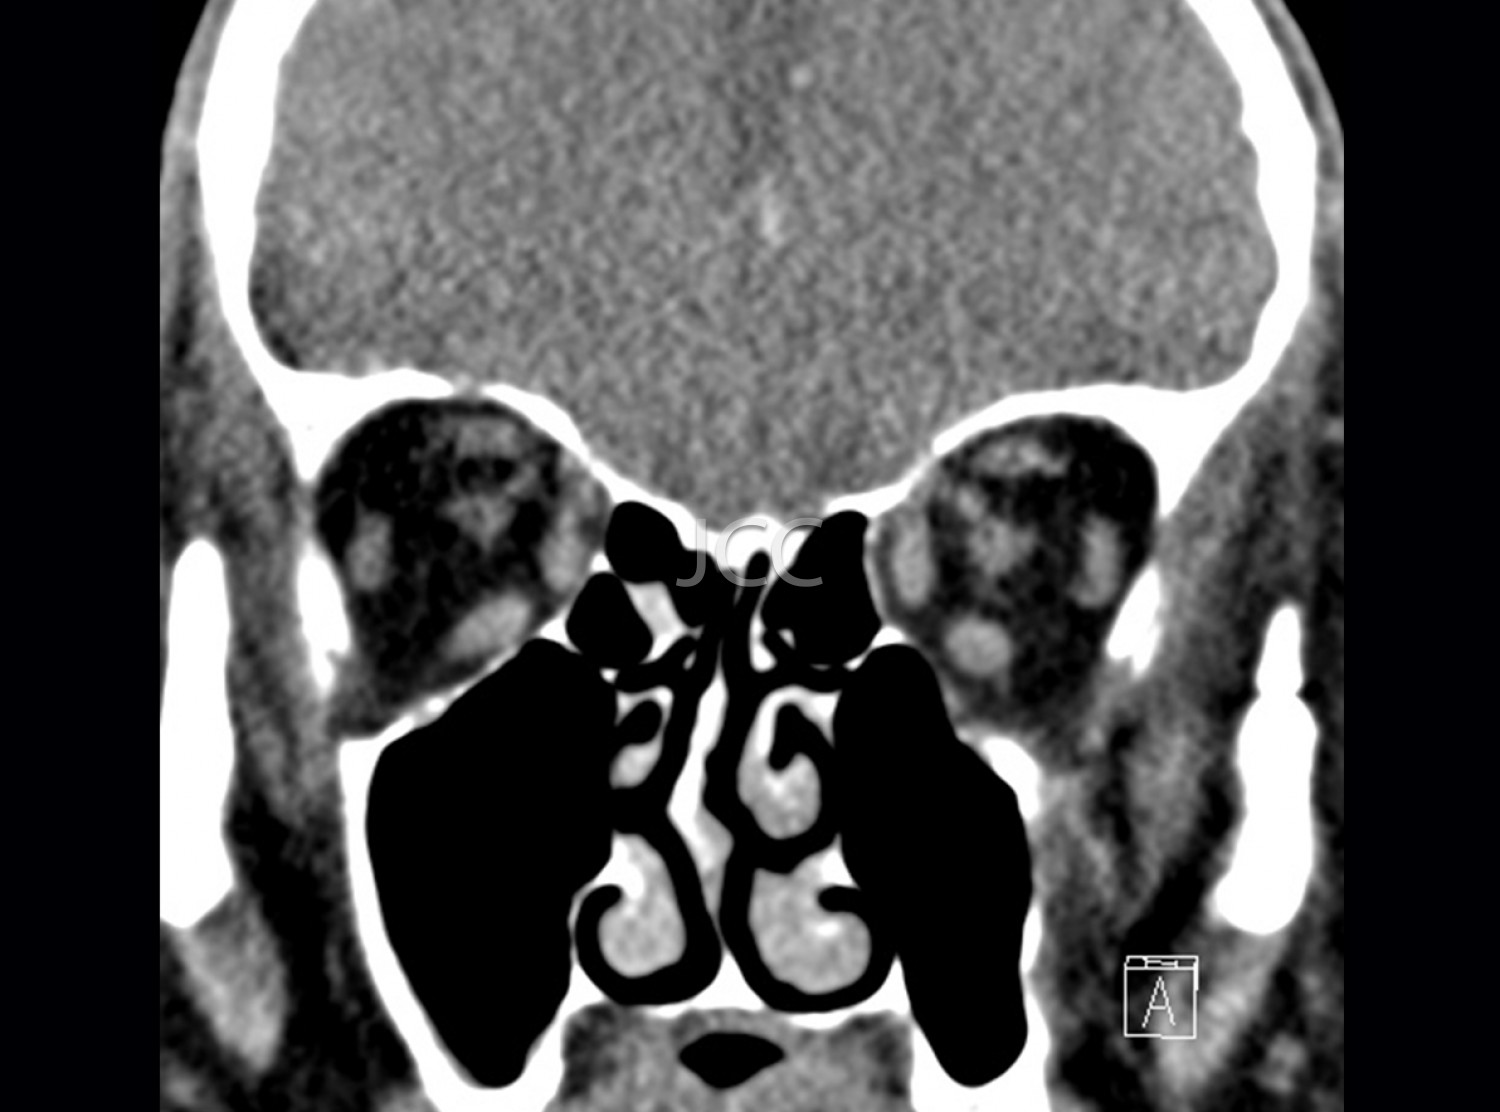

Computed Axial Tomography - Orbits CAT scan